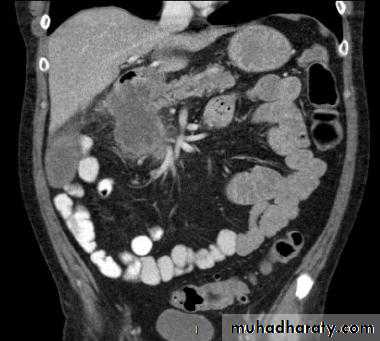

Colorectal carcinoma

• Colorectal carcinoma (CRC) is the second leading cause of cancer death in Western society.

• CRC may present clinically with large bowel obstruction, GIT bleeding, or less specifically with weight loss or anemia.

• A large percentage of CRC show locally invasive disease or distant metastases at the time of presentation.

• CT of the abdomen is the imaging investigation of choice for detection of locally invasive disease, lymphadenopathy and distant metastases in patients with CRC.

• CT is unable to assess the depth of wall invasion or detect small metastases in non-enlarged lymph nodes. Therefore, CT is accurate for advanced disease though less so for earlier noninvasive disease.